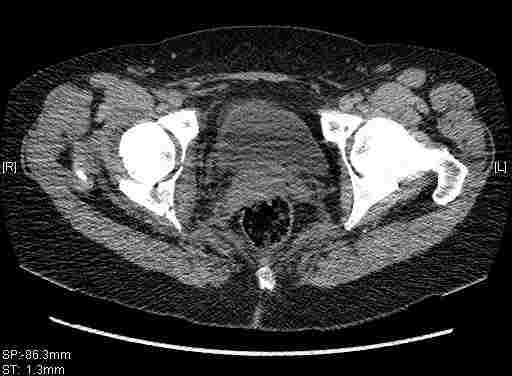

Женщина,58 лет, после ДТП 6 суток. Первично повреждение расценено как переломы ветвей лонной кости. После подтверждения повреждения вертлужной впадины,как чаще всего случается, вопрос встал о тактике. БОльшинство за консерватиное лечение.К сожалению кт у нас "во время" сломался. Прилагаю стандартные снимки вертлужки. У меня следующие вопросы к коллегам:1. Правильно ли рассценивать это повреждение как Т-образный перелом вертлужнй впадины?2. Можно ли добиться анатомической репозиции поверхности вертлужной впадины скелетным вытяжением в данном случае, если нет, что будет этому препятствовать?3. Если смещение останется таким как сейчас, через какое время появится необходимость эндопротезирования (по вашему опыту)?Спасибо.

Удалось сегодня вывести пациентку в соседнюю больницу, где есть кт. Срезы сделаны только горизонтальные.

|

Приветствую,Антон.Рункова рядом нет,но после полученных данных КТ,обсуждали совместно.Итог обсуждения-развернутый ответ дать не получится,т.к.срезы выбраны не информативные.Если ориентироваться на данные 3D,то ,ИМХО,можно лечить на вытяжении.